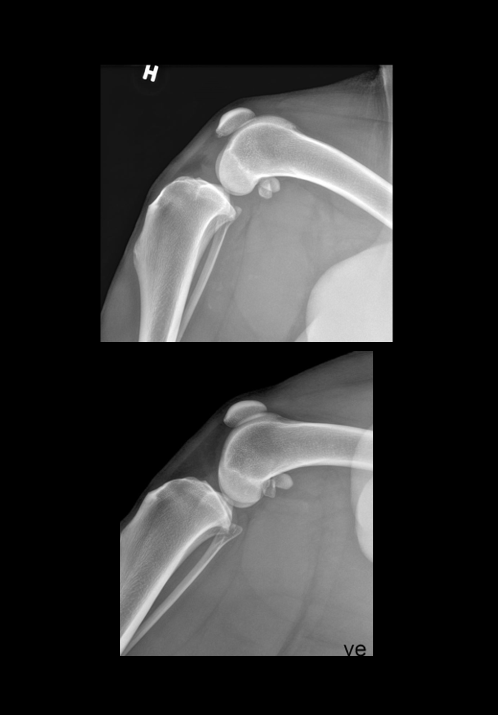

Signalement: Golden retriever, hannhund, 9år. Anamnese: Kom løpende ute og bommet på en trapp opp til en veranda. Hylte til og var akutt 5/5 grader halt på høyre bakbein. Redusert til 3-4/5 ila 30 min. Fått NSAIDs og holdt i ro. Kliniske funn: 2/5 grader halt i skritt, får NSAIDs. Mild til moderat fylning i høyre kneledd. Mild positiv “tibial thrust” på flektert kne, får ikke frem på ekstendert kne.